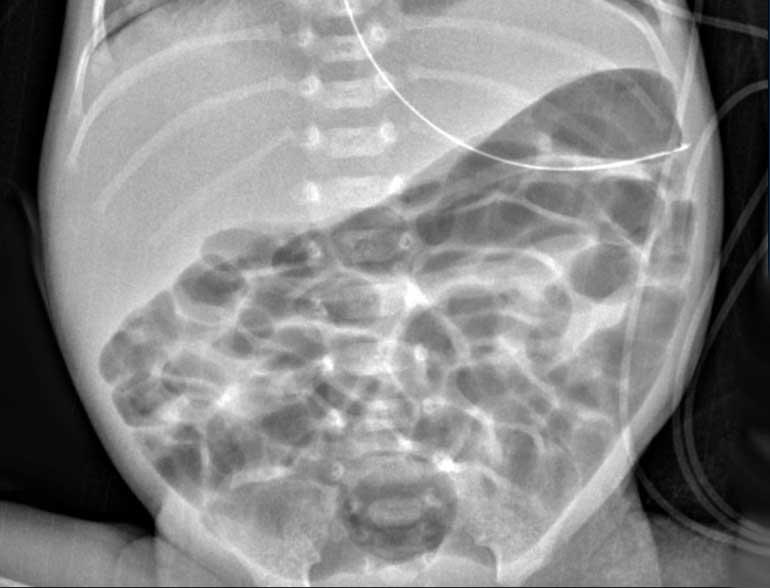

Quai ruột cố định

Quai ruột cố định là quai ruột không thay đổi theo thời gian trên X-quang.

Đây là dấu hiệu đáng lo ngại, phù hợp với hoại tử ruột và do đó là dấu hiệu báo trước nguy cơ thủng sắp xảy ra.

Nhu động ruột tất nhiên có thể được đánh giá tốt nhất bằng siêu âm.

Hình ảnh

Hai phim X-quang chụp cách nhau vài giờ cho thấy ở vùng bụng trên chỉ có các quai ruột giãn nhẹ nhưng không có nếp niêm mạc, không thay đổi theo thời gian. Đây là dấu hiệu của vắng mặt nhu động ruột.

Lịch chụp lại được khuyến cáo là mỗi 6-8 giờ, nhưng tất nhiên phụ thuộc vào tình trạng lâm sàng.

Một ví dụ khác về quai ruột cố định.